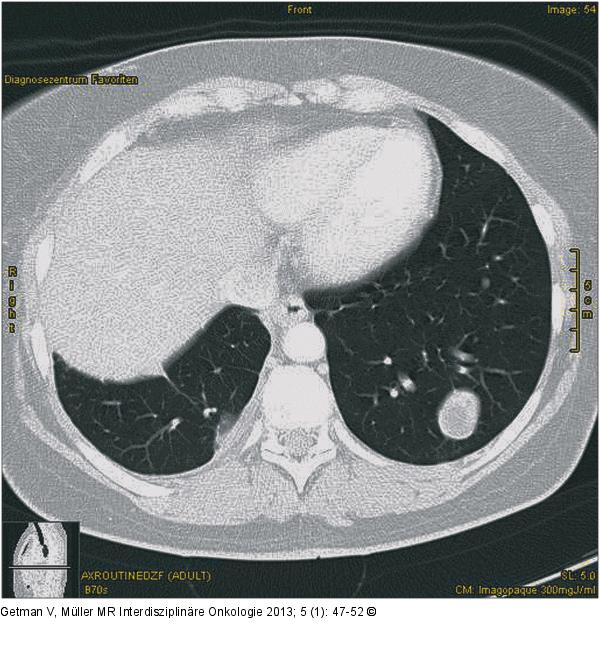

Abbildung 1: Thorax-CT Thorax-CT mit solitärer Metastase im linken Lungenunterlappen. |

Thorax-CT mit solitärer Metastase im linken Lungenunterlappen. |